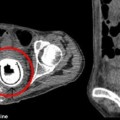

Thị lực của Ian Tibbetts đã được khôi phục tới 40% sau ca phẫu thuật có tên khoa học là osteo-ondonto-keratoprothesis và được thực hiện bởi giáo sư Christopher Lio của bệnh viện mắt hạt Sussex ở miền nam nước Anh. Osteo-ondonto-keratoprothesis là hình thức duy nhất của phẫu thuật giác mạc nhân tạo cho những bệnh nhân ở tình trạng nghiêm trọng nhất.

Theo Nine MSN, sau khi lấy răng bệnh nhân và khoan một cái lỗ ở giữa, các bác sĩ sẽ chèn giác mạc nhân tạo bằng plastic vào trong lỗ trước khi đặt cái răng dưới hốc mắt để nó phát triển mô. Sau vài tháng, cái răng sẽ được cấy vào mắt và giúp bệnh nhân nhìn thấy trở lại.